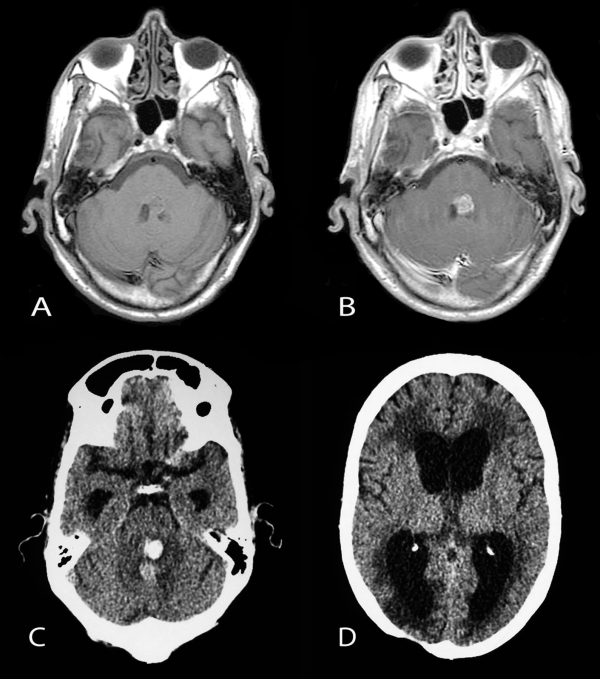

PA是兒童年齡組中常見的神經膠質瘤,它主要發(fā)生在幼兒(中位年齡為4歲)中。PA在后顱窩、視神經通路、背側分葉狀、外生性腦干腫瘤中所占比重較大,在t1加權像上通常表現為低張力囊性腫塊,實性部分增強明亮(圖1)。

顱腦磁共振MR

圖1。術前(a)和術后(b)顱腦磁共振MR,術前MR顯示右側丘腦較大囊實性占位,膠質瘤可能,皮質脊髓束(負責人體肢體運動的神經傳導束)受壓,腦室擴大,術后MR顯示腫瘤全切,腦組織復位,無腦出血、腦水腫等損傷。

(1)神經節(jié)神經膠質瘤(WHO I級)是較常見的致癲癇性腫瘤,盡管它僅占全部腦腫瘤的1-4%。它往往發(fā)生在具有長期癲癇病史的兒童和年輕人中,通常難以憑借藥物控制。復雜的部分發(fā)作較為常見。盡管神經節(jié)膠質瘤傾向于出現在顳葉,但它可發(fā)生在神經軸的任何地方,包括頸髓連接處、松果體和鞍上區(qū)域。顳部外的位置與組織學異型性和間變性相關(間變性神經節(jié)膠質瘤;手術是這些腫瘤的主要治療手段[見圖3] )。雖然有報道稱有惡性變可能,但其通常是良性的。幕上神經節(jié)膠質瘤通??梢允中g全切,因此這是可治愈的,也為80%的患者達成了Engel I型發(fā)作結局。為了進一步好轉癲癇發(fā)作的控制,建議行腦損傷切除聯合鄰近顳部新皮質切除術,腫瘤全切的主要障礙是腫瘤的中線位置(如腦干),而其他限制因素包括分界差、靠近主皮層和浸潤了重要結構。

右顳部腫瘤

圖3。11歲患兒,右顳部腫瘤多發(fā)囊腫并增強強化的實性瘤體部分,術前和術后軸位t1加權MRI對比,提示腫瘤被完全切除,較終病理診斷為神經節(jié)膠質瘤。